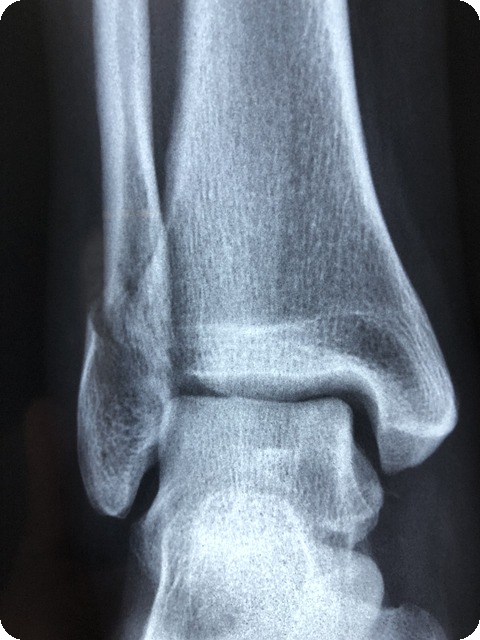

부상 예방을 위한 발목 관리

발목은 다양한 움직임을 지원하지만, 동시에 부상에 매우 취약한 부위이기도 합니다. 발목의 부상은 일상적인 활동뿐만 아니라 운동 중에도 큰 불편을 초래할 수 있습니다. 따라서 부상의 위험을 줄이기 위한 발목 관리는 꼭 필요합니다.

발목의 역할과 기능

발목은 우리의 움직임에 중요한 역할을 하고 있습니다. 발목은 하체의 다른 부위들과 연결되어 있으며, 걷기, 뛰기, 서기 등의 기본적인 동작을 지원합니다. 발목이 약해지면 일상적인 움직임에도 불편함을 느낄 수 있으며, 이는 곧 하체의 다른 부위에도 부정적인 영향을 미칩니다.

발목의 주된 기능은 다음과 같습니다:

- 지지력: 체중을 지탱하며 하중을 분산시킵니다.

- 유연성: 다양한 움직임을 가능하게 합니다.

- 균형 유지: 안정성을 제공해 우리의 균형을 지켜줍니다.